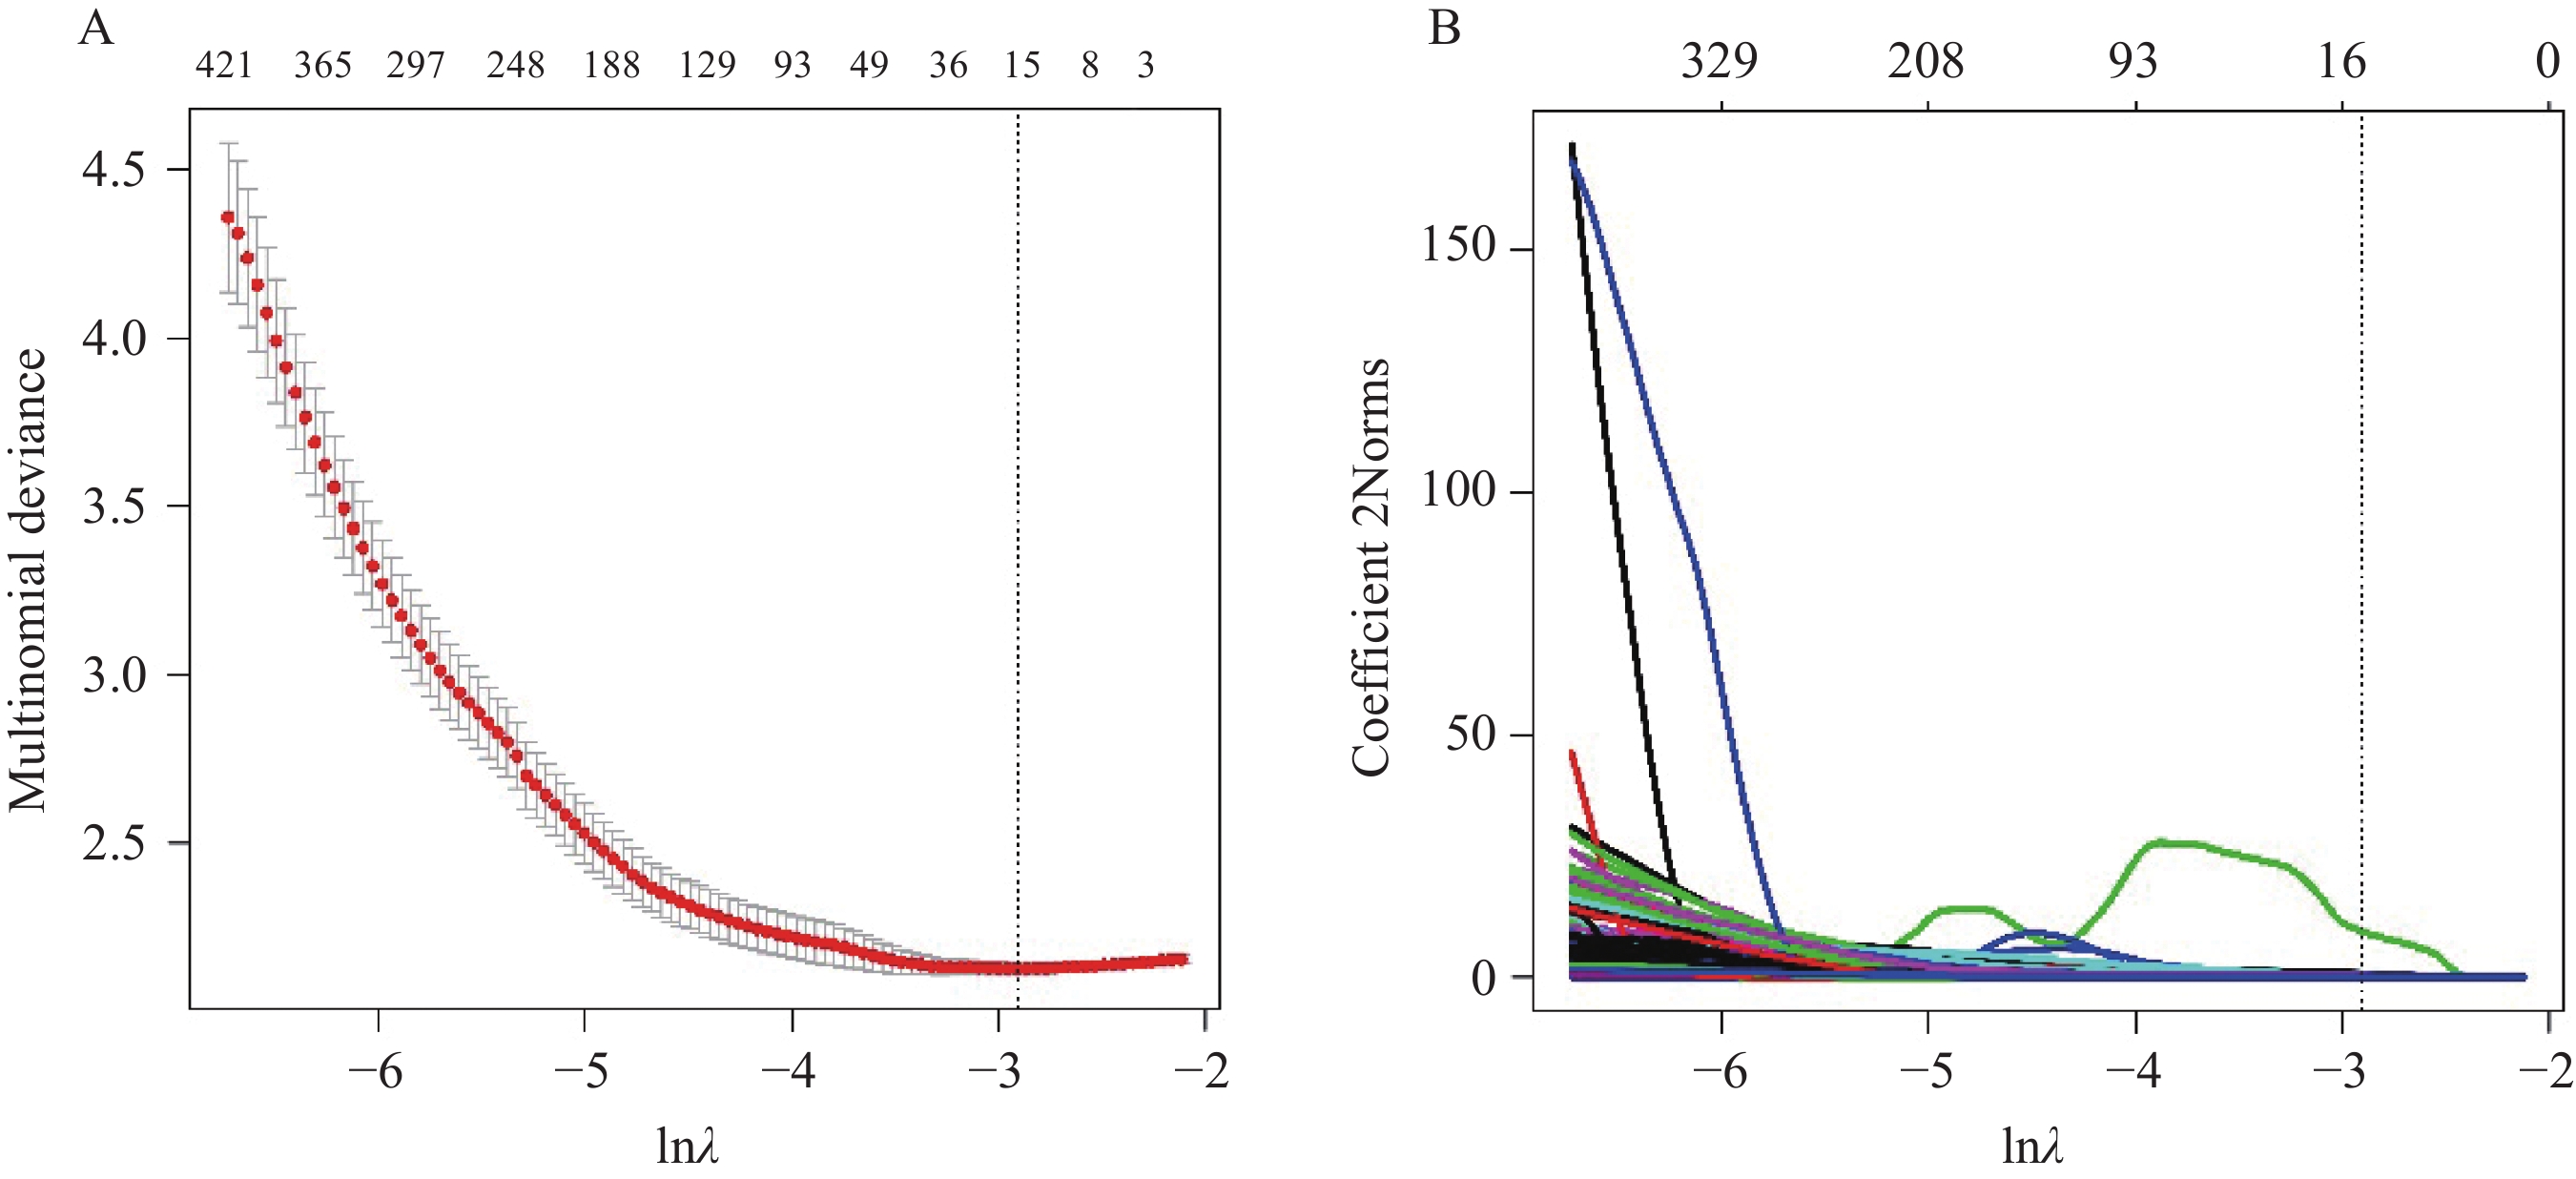

每个PTC共提取1 899个影像组学特征,采用LASSO回归进行特征降维,经交叉验证确定最优λ值为

0.05445745 (lnλ= −2.910),见图2。最终共筛选出15个影像组学特征,其中一阶特征3个、形状特征2个、灰度共生矩阵特征7个、灰度行程矩阵特征2个、灰度大小区域矩阵特征1个,分别为original_firstorder_Kurtosis、original_firstorder_MeanAbsoluteDeviation、original_firstorder_Variance、original_shape_Elongation、original_shape_MaximumDiameter、original_glcm_Idmn、original_glcm_MaximumProbability、original_glcm_SumEntropy、original_glcm_DifferenceVariance、curvatureflow_glcm_Imc2、wavelet_glcm_wavelet-LLH-DifferenceVariance、wavelet_glcm_DifferenceAverage、wavelet_glrlm_wavelet-HLH-GrayLevelVariance、discretegaussian_glrlm_LowGrayLevelRunEmphasis及original_glszm_GrayLevelNonUniformity。![]() 图 2 甲状腺乳头状癌提取影像组学特征的LASSO回归交叉验证图及回归系数图Figure 2 Lasso regression cross-validation diagram and regression coefficient diagram for extracting radiomic features of papillary thyroid carcinomaA: optimal lnλ value determined by cross-validation (the lowest multinomial deviance); B: an increase in lnλ value causes a change in the radiomic feature coefficients; optimal lnλ value (vertical dashed line) corresponds to the number of radiomic features (upper horizontal axis).

图 2 甲状腺乳头状癌提取影像组学特征的LASSO回归交叉验证图及回归系数图Figure 2 Lasso regression cross-validation diagram and regression coefficient diagram for extracting radiomic features of papillary thyroid carcinomaA: optimal lnλ value determined by cross-validation (the lowest multinomial deviance); B: an increase in lnλ value causes a change in the radiomic feature coefficients; optimal lnλ value (vertical dashed line) corresponds to the number of radiomic features (upper horizontal axis).2.3 DNN建模及性能